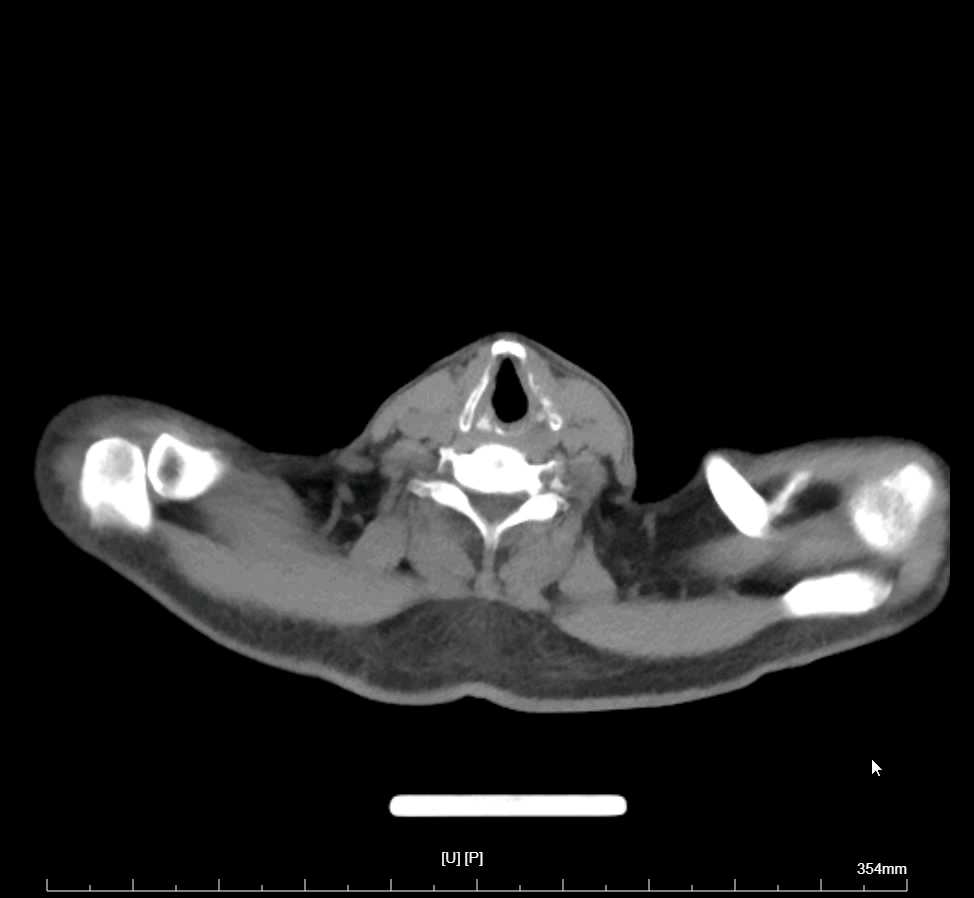

李梦杰huxi 达人已点赞患者性别:男性。

患者年龄:68岁。

主诉:反复畏寒,发热伴咳嗽4天

简要病史:有脑梗死病史半年余,现遗留左侧肢体无力,有高血压病史

辅助检查:

现患者就是一直发烧,最好体温38.2,血常规,超敏c,降钙素,心肌酶都正常